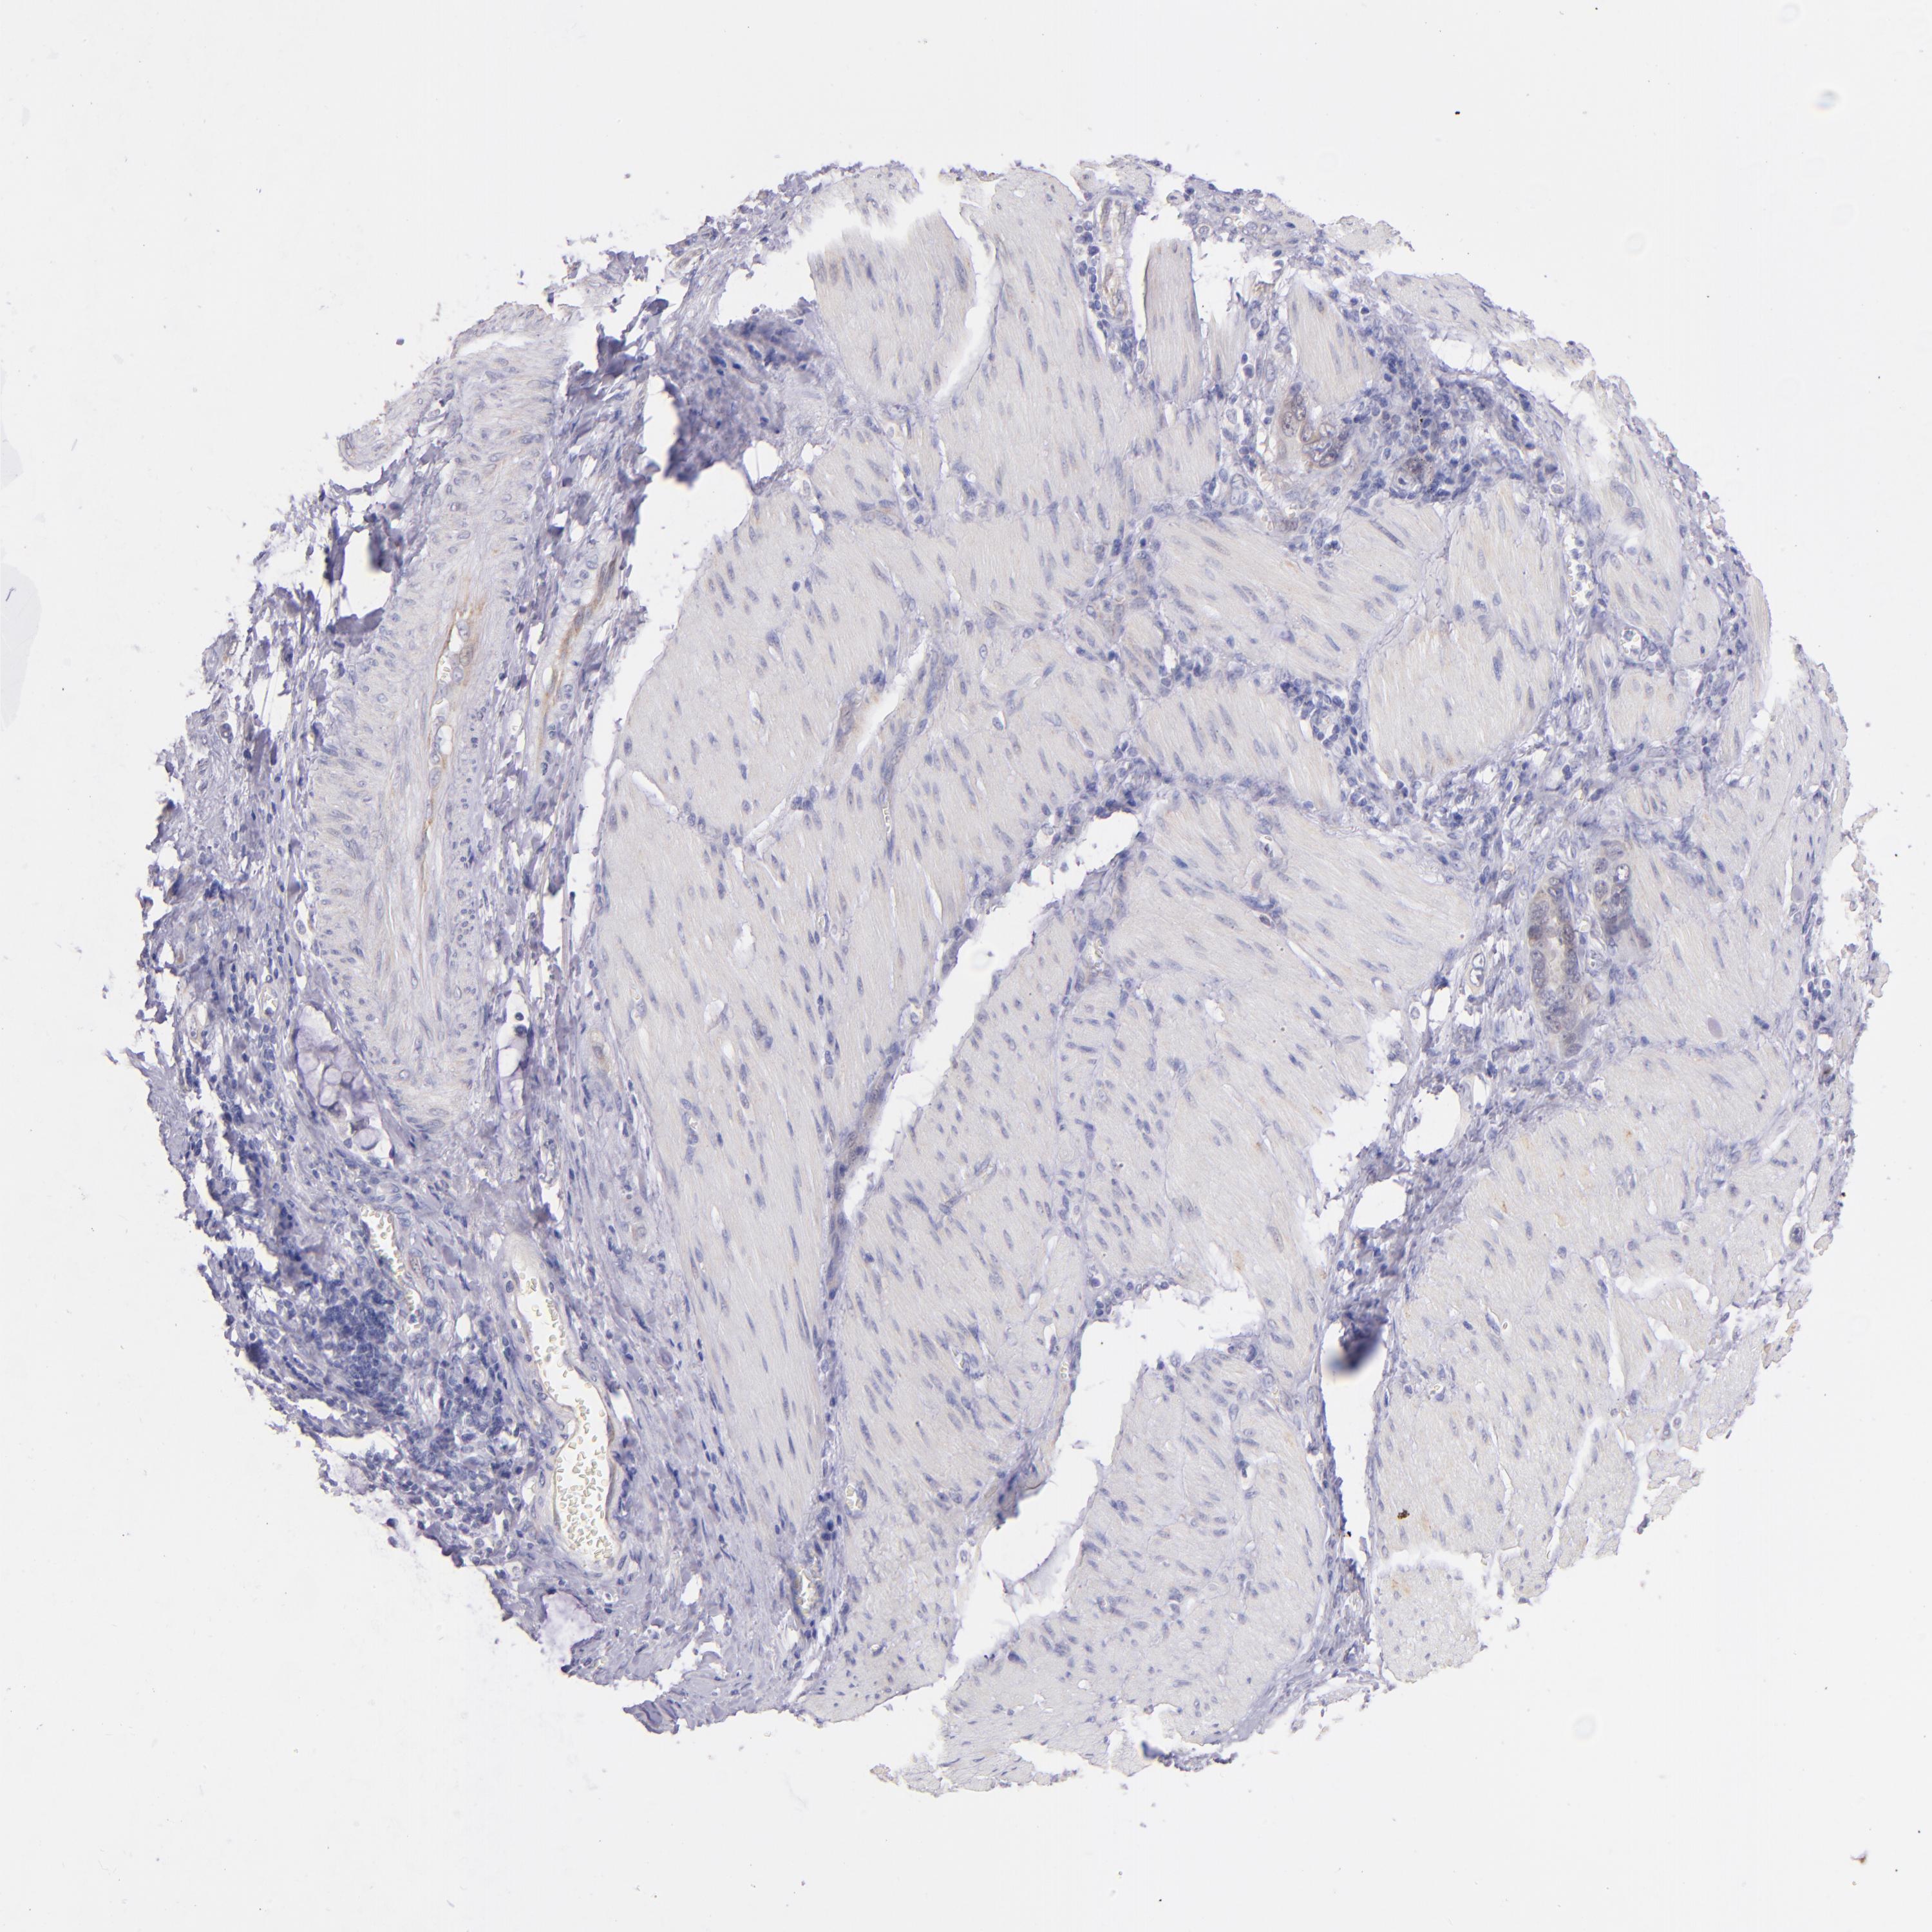

STOMACH CANCER - Protein expressioni

A mouse-over function shows sample information and annotation data. Click on an image to view it in a full screen mode. Samples can be filtered based on level of antibody staining by selecting one or several of the following categories: high, medium, low and not detected. The assay and annotation is described here.

Note that samples used for immunohistochemistry by the Human Protein Atlas do not correspond to samples in the TCGA dataset.

Antibody stainingi

Antibody staining in the annotated cell types in the current human tissue is reported as not detected, low, medium, or high, based on conventional immunohistochemistry profiling in selected tissues. This score is based on the combination of the staining intensity and fraction of stained cells.

Each image is clickable and will lead to virtual microscopy that enables deeper exploration of all samples and also displays staining intensity scores, fraction scores and subcellular localization as well as patient and tissue information for each sample.

Antibody HPA001871

Antibody HPA001919

Staining

High

Medium

Low

Not detected

Intensity

Strong

Moderate

Weak

Negative

Quantity

>75%

75%-25%

<25%

None

Location

Nuclear

Cytoplasmic/membranous

Cytoplasmic/membranous,nuclear

Adenocarcinoma, NOS